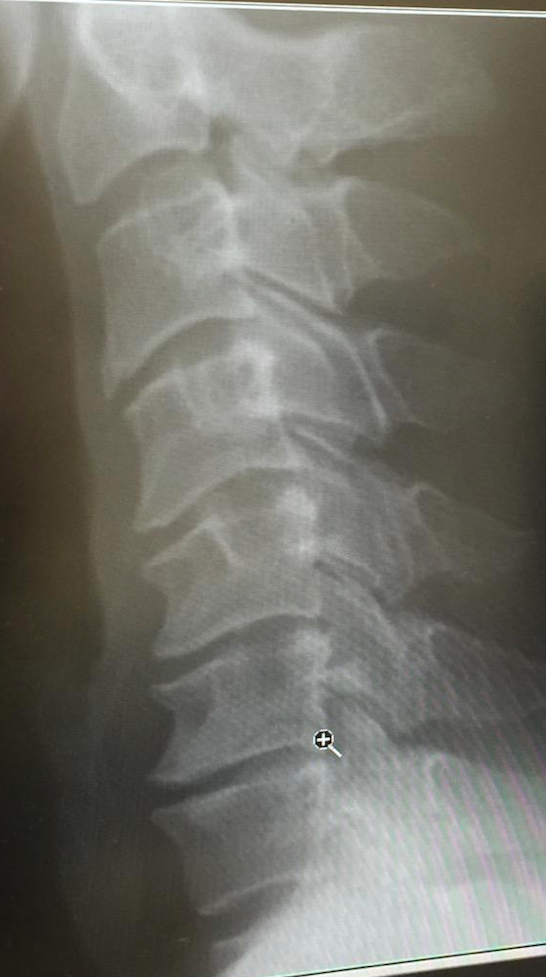

これがボクの今の頚椎のレントゲン写真だ。

下のほうの骨の隙間がつまっていて、牽引しないと朝になっても頭をあげられないことがよくある。